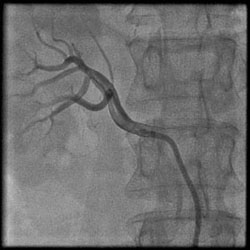

2、腎動脈狹窄 可為單側或雙側性。病變性質可為先天性、炎症二指性或動脈粥樣硬化性,後者見於老年人,前兩者主要見於青少年。反進展迅速的高血壓或高血壓突然加重,呈惡性高血壓表現,藥物治療無效,均應懷疑本症。本症多有舒張壓力中、重度升高,體檢時可在上腹部或背部肋脊處聞及血管雜音。大劑量斷層靜脈腎盂造影、放射性核素腎圖有助於診斷,腎動脈造影可明確診斷。

4、大劑量斷層靜脈腎盂造影、放射性核素腎圖有助於診斷,腎動脈造影可明確診斷腎動脈狹窄。

2、ACE抑制劑對腎臟有保護作用,除降低血壓外,還可減少蛋白尿,延緩腎功能惡化。腎動脈狹窄治療包括手術、經皮腎動脈成形術(PTRA)和藥物治療。手術治療包括血流重建術、腎移植術、腎切除術。經皮腎動脈成形術手術簡便、療效好,為首選治療。不適宜上述治療者只能用藥物治療以降低血壓,ACE抑制劑有降壓效果,但可能使腎小球濾過率進一步降低,使腎功能惡化,尤其對雙側腎動脈狹窄不宜套用。鈣通道阻滯劑有降壓作用,並不明顯影響腎功能。